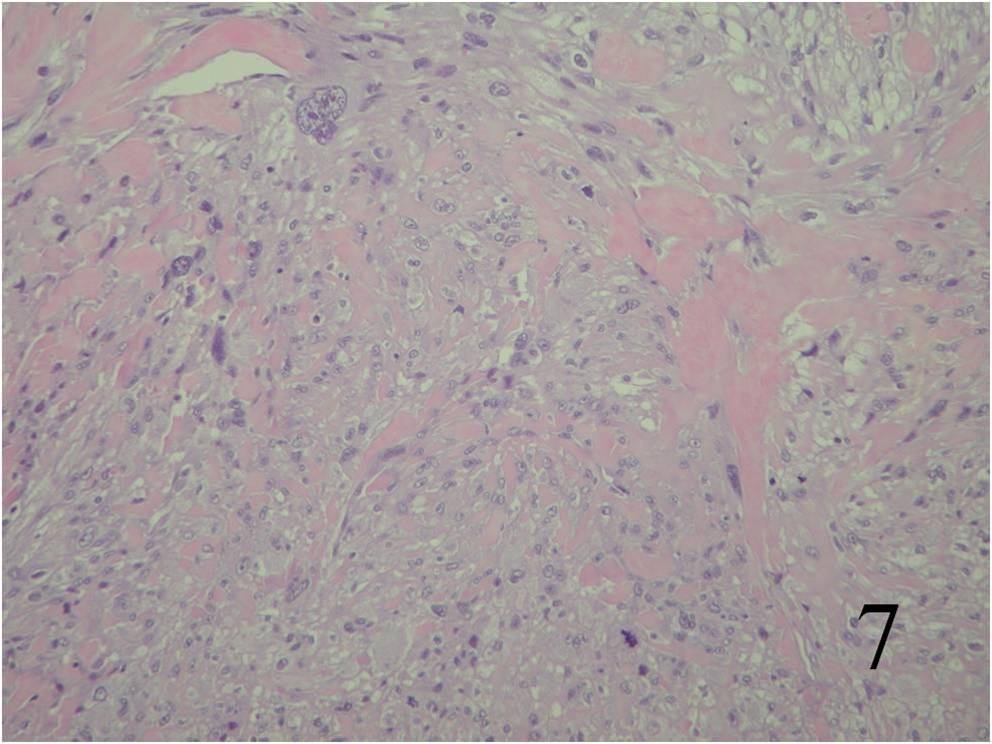

Microscopic

Large variation in differentiation, from obvious smooth muscle differentiation to an appearance similar to MFH (Fig. 7,8)

Moderately cellular, with elongated cells and eosinophilic cytoplasm

Cells are arranged in fascicles, with giant cells (giant cells often resemble osteoclasts)

The nuclei look elongated and can have an appearance similar to a corkscrew with round ends

Fig. 7 Microscopic: Low and High (Fig. 8) power magnification of a leiomyosarcoma showing palisading spindle cells; with eosinophilic cytoplasm. Immunohistochemical stains for leiomyosarcoma are positive stain for actin (Fig. 9) and desmin (Fig. 10)